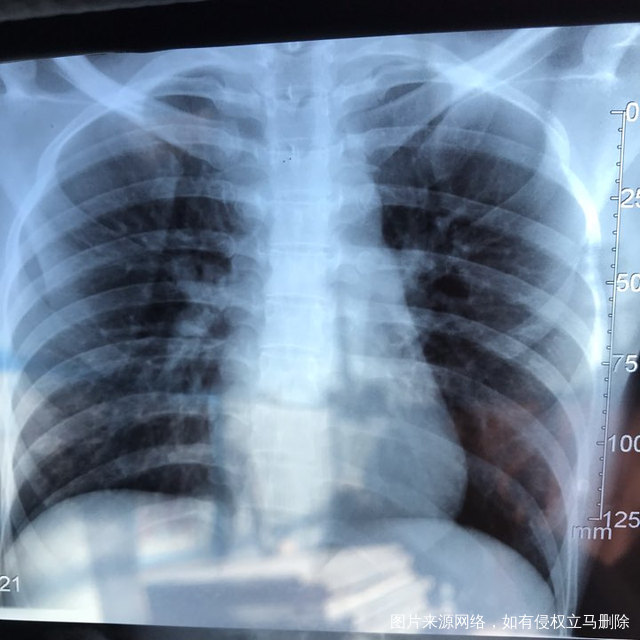

麻烦各位教授给我看看输卵管造影片子,谢谢了🙏